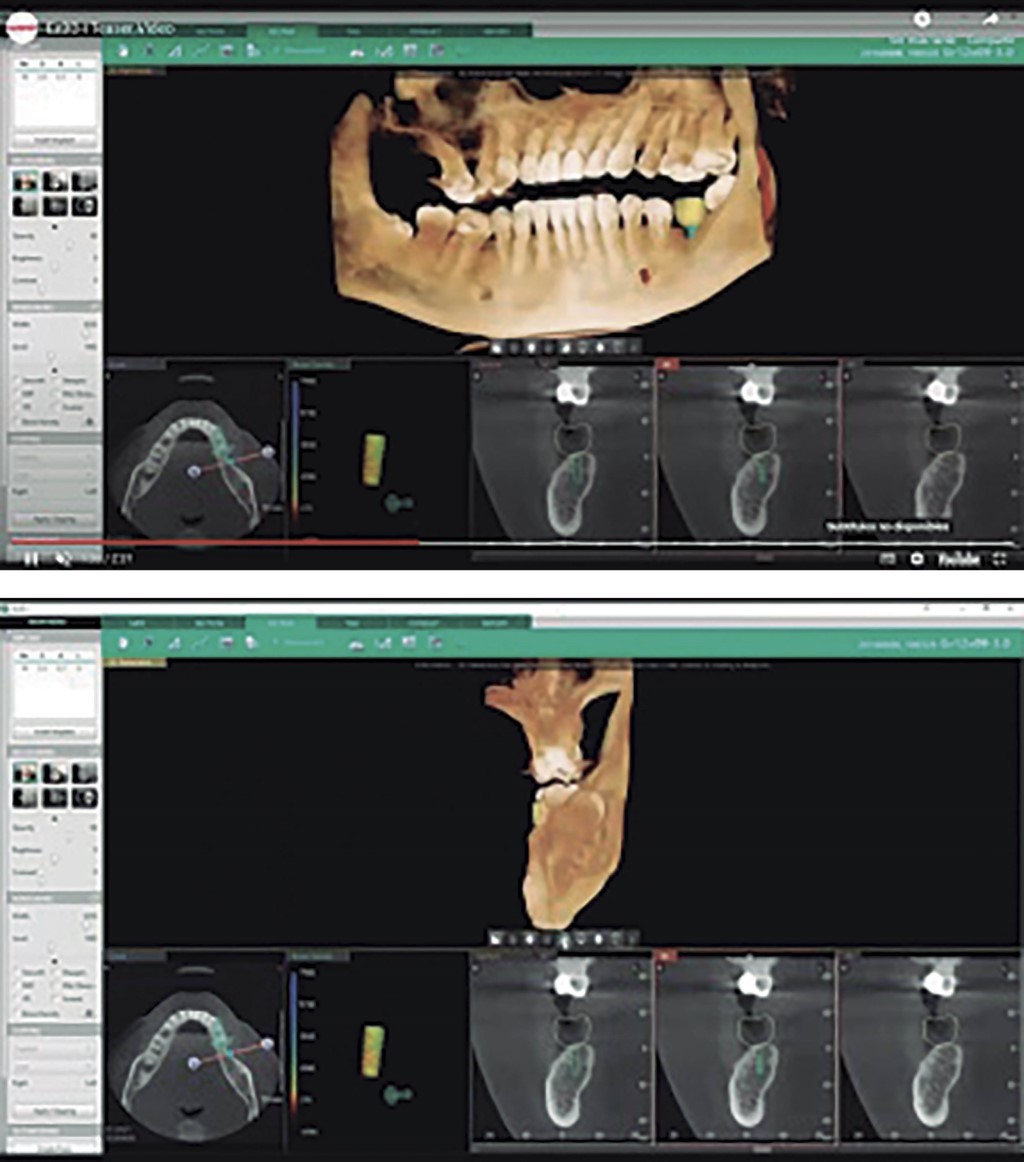

Artificial intelligence, uses of software and its applications in dental radiology.

Introduction: artificial intelligence (AI) is used in different fields, such as medicine, with multiple results, so the use developed in dental radiology can add importance to the dental profession. Objective: the purpose of this work was to identify the various artificial intelligence software applications in dental radiology. Material and methods: an electronic review of the information related to AI software applied in dental radiology was carried out. The inclusion criteria consisted of AI-based technology in dental x-rays and their applications in dental practice. Results: within the AI software, we could find the following: AI Dental Image from Carestream, Pearl by DentalMonitoring, Vizi AI from Vatech, and Diagnocat: Promadent AI Insights. And some companies that use AI in dental radiology, such as Zebra Medical Vision, Allisone Technologies, and DentiMax, With the following applications in dental radiology, they improve diagnostic accuracy, workflow efficiency, detect dental problems at an early stage, diagnose cavities, gum diseases, dental fractures, and maxillofacial tumors, and also support density measurement of bones and the location of cephalometric reference points. Conclusions: in the last decade, multiple AI software programs have been developed that have the potential to revolutionize dental radiology. By improving diagnostic accuracy and early detection of dental problems, AI can help dentists provide more accurate and safer dental care to their patients.

Figure 2